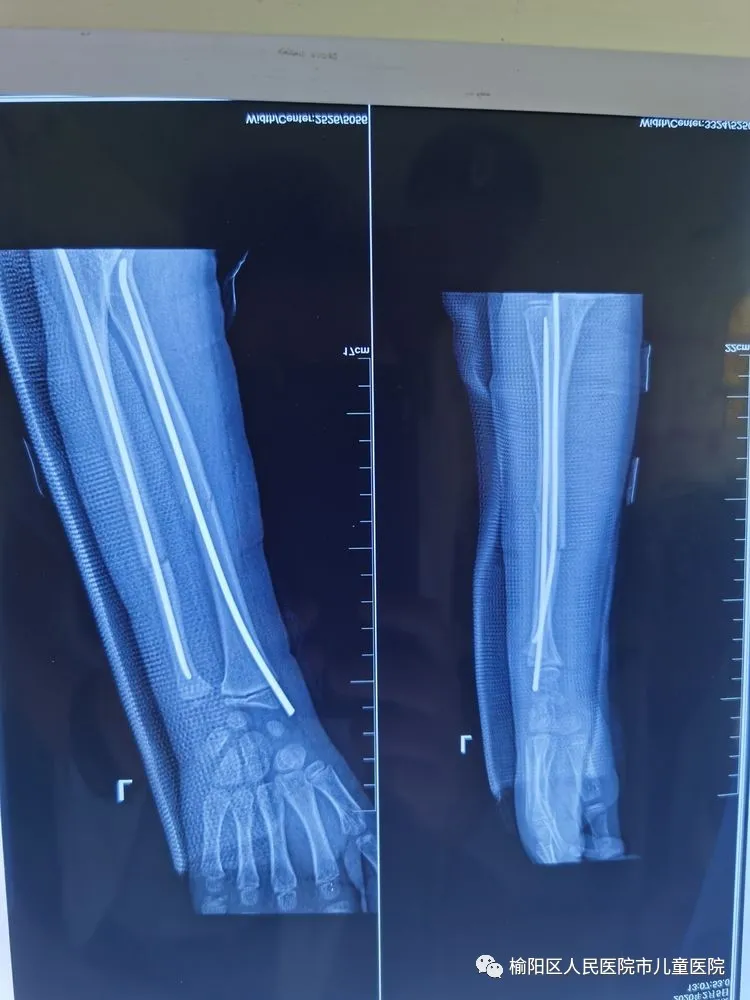

在全麻下行弹性髄内针微创闭合治疗

0.5cm的微创小口

术后5个月,完美愈合。